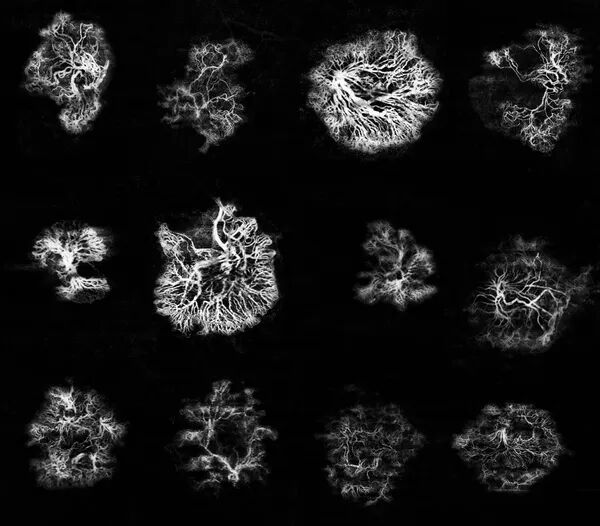

My presentation, entitled “Gene therapy for Neovascular AMD: are we moving toward a cure?”, provided an opportunity to review recent advances in gene therapy applied to neovascular AMD.

I discussed:

• the clinical data currently available,

• the limitations that must be considered when interpreting results,

• and the perspectives that may guide the next stages of development.